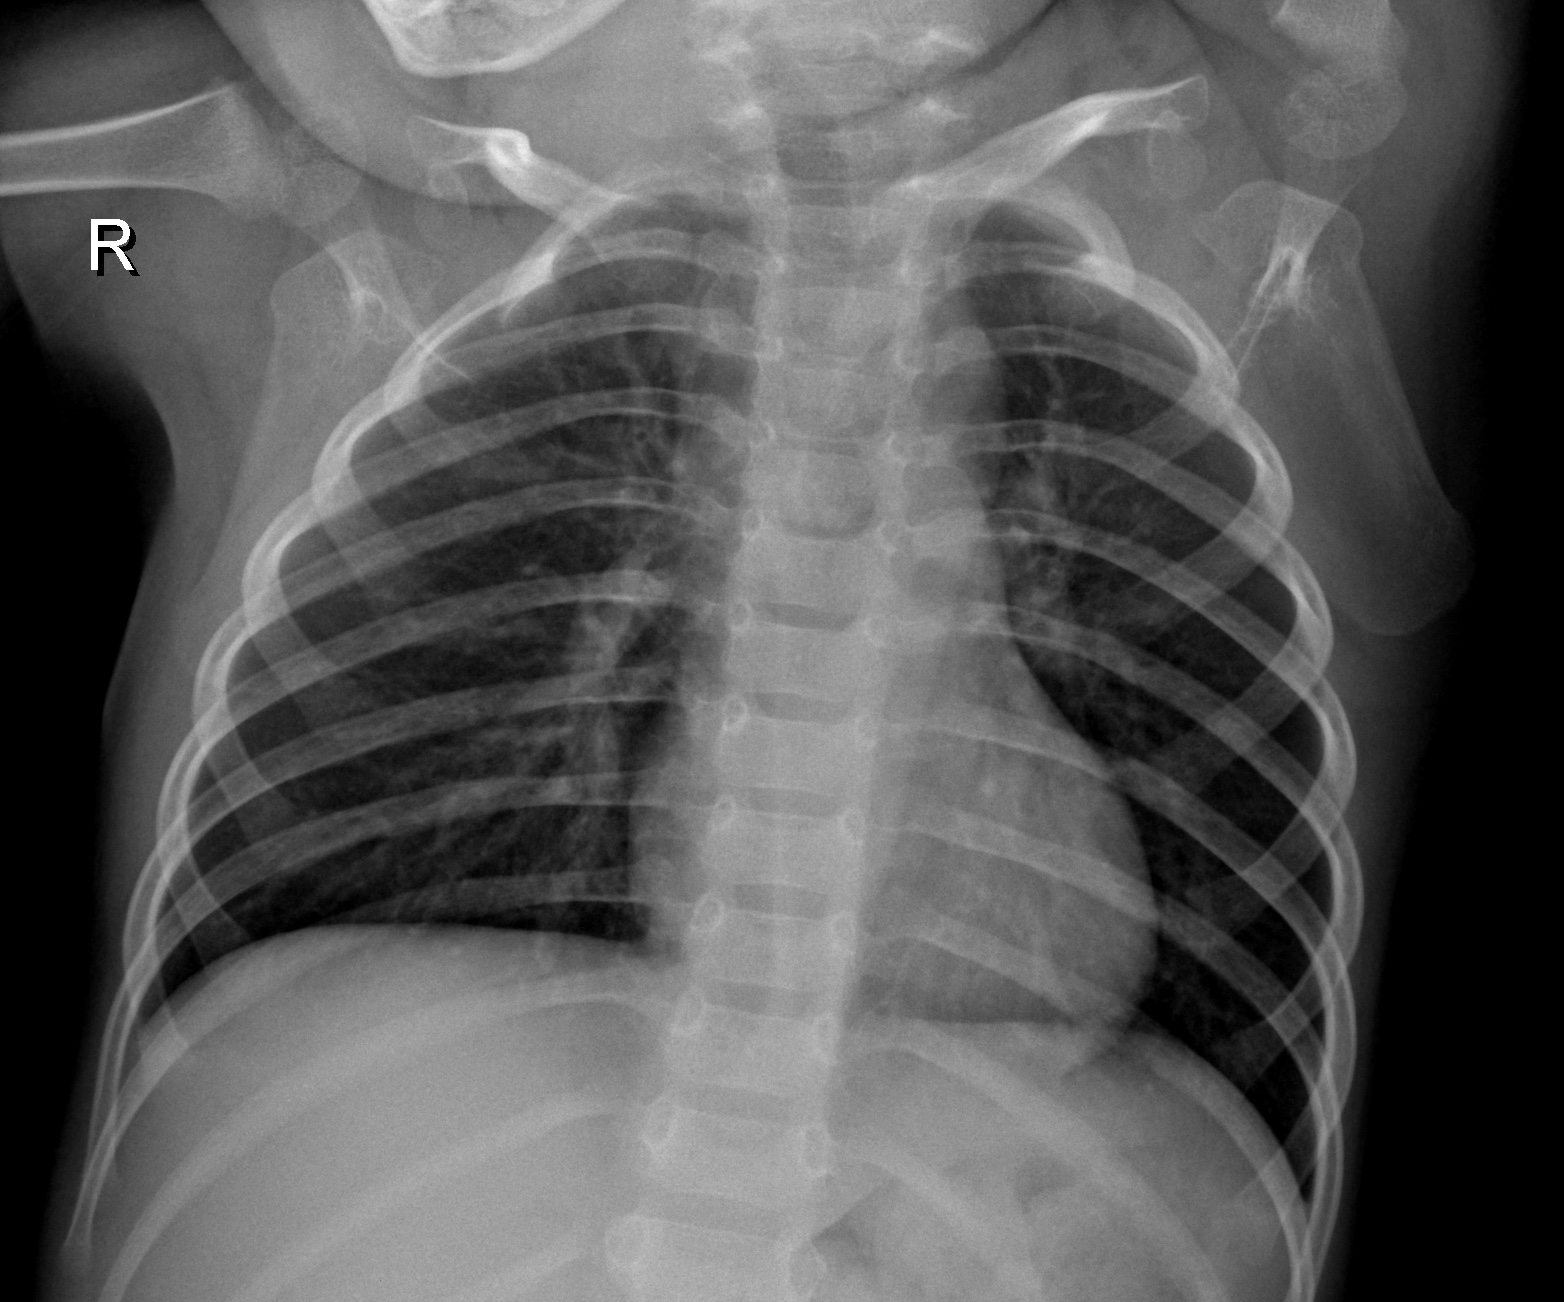

Pneumonia is an acute pulmonary infection that can be caused by bacteria, viruses, or fungi and infects the lungs, causing inflammation of the air sacs and pleural effusion, a condition in which the lung is filled with fluid. It accounts for more than 15% of deaths in children under the age of five years. Pneumonia is most common in underdeveloped and developing countries, where overpopulation, pollution, and unhygienic environmental conditions exacerbate the situation, and medical resources are scanty. Therefore, early diagnosis and management can play a pivotal role in preventing the disease from becoming fatal. Radiological examination of the lungs using computed tomography (CT), magnetic resonance imaging (MRI), or radiography (X-rays) is frequently used for diagnosis. X-ray imaging constitutes a non-invasive and relatively inexpensive examination of the lungs. Fig 1 shows an example of a pneumonic and a healthy lung X-ray. The white spots in the pneumonic X-ray (indicated with red arrows), called infiltrates, distinguish a pneumonic from a healthy condition. However, chest X-ray examinations for pneumonia detection are prone to subjective variability. Thus, an automated system for the detection of pneumonia is required. In this study, we developed a computer-aided diagnosis (CAD) system that uses an ensemble of deep transfer learning models for the accurate classification of chest X-ray images. Deep learning is an important artificial intelligence tool, which plays a crucial role in solving many complex computers vision problems.